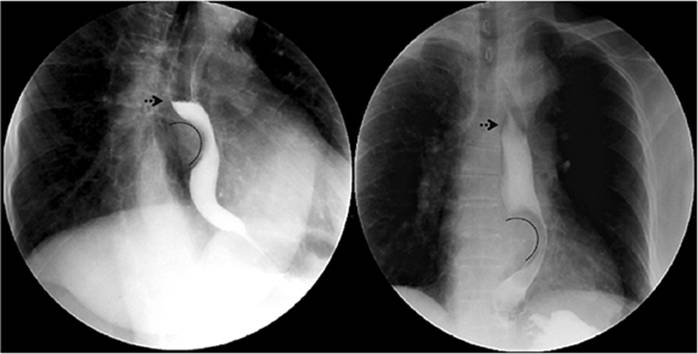

Trastornos de la motilidad esofágica

Los trastornos motores esofágicos constituyen una amplia variedad de padecimientos poco frecuentes de etiología aún desconocida. El uso del esofagograma demuestra una gran sensibilidad para el diagnóstico de una parte de los trastornos funcionales de la motilidad, pero su diagnóstico definitivo depende de los hallazgos de la manometría clásica o de alta resolución 13,14. La acalasia es una enfermedad crónica y progresiva caracterizada por una falla en la relajación del esfínter esofágico inferior, ausencia de peristalsis y aumento de la presión esofágica intraluminal 14,15 (Figura 6).

A pesar de esto, aproximadamente el 20% al 30 % de los pacientes con este diagnóstico y con hallazgos típicos radiológicos no presentan disfunción en el esfínter esofágico inferior 10,14. El espasmo esofágico difuso se presenta con contracciones no coordinadas y dolor retroesternal, y el esófago en cascanueces, con onda de propagación normal, pero con una fuerza de contracción mayor, con una duración aumentada de la contracción 14,15,16 (Figura 6). En los pacientes con espasmo esofágico difuso, las contracciones peristálticas, por su presentación intermitente, se presentan en menos del 15% de los casos 10,14.